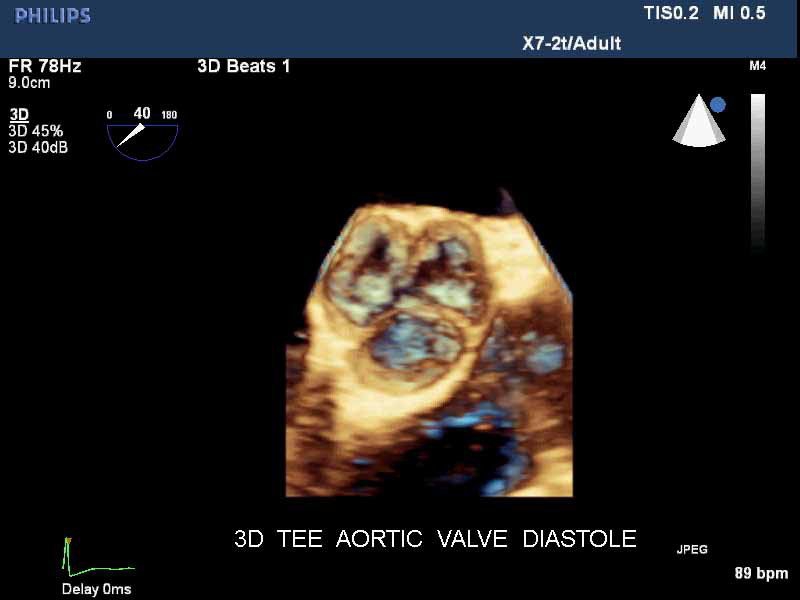

• Чреспищеводная эхокардиография

• Live 3D TEE: Эта функция позволяет проводить чреспищеводную эхокардиографию в режиме реального времени, что позволяет оценить механические сокращения сердца с точностью, необходимой для оценки результатов хирургического вмешательства.

• 3D эхо-кг в реальном времени (Live3DEcho): Эта технология позволяет получать объемные 3D изображения сердца в режиме реального времени.

• Чреспищеводный УЗИ датчик Philips Х7-2T